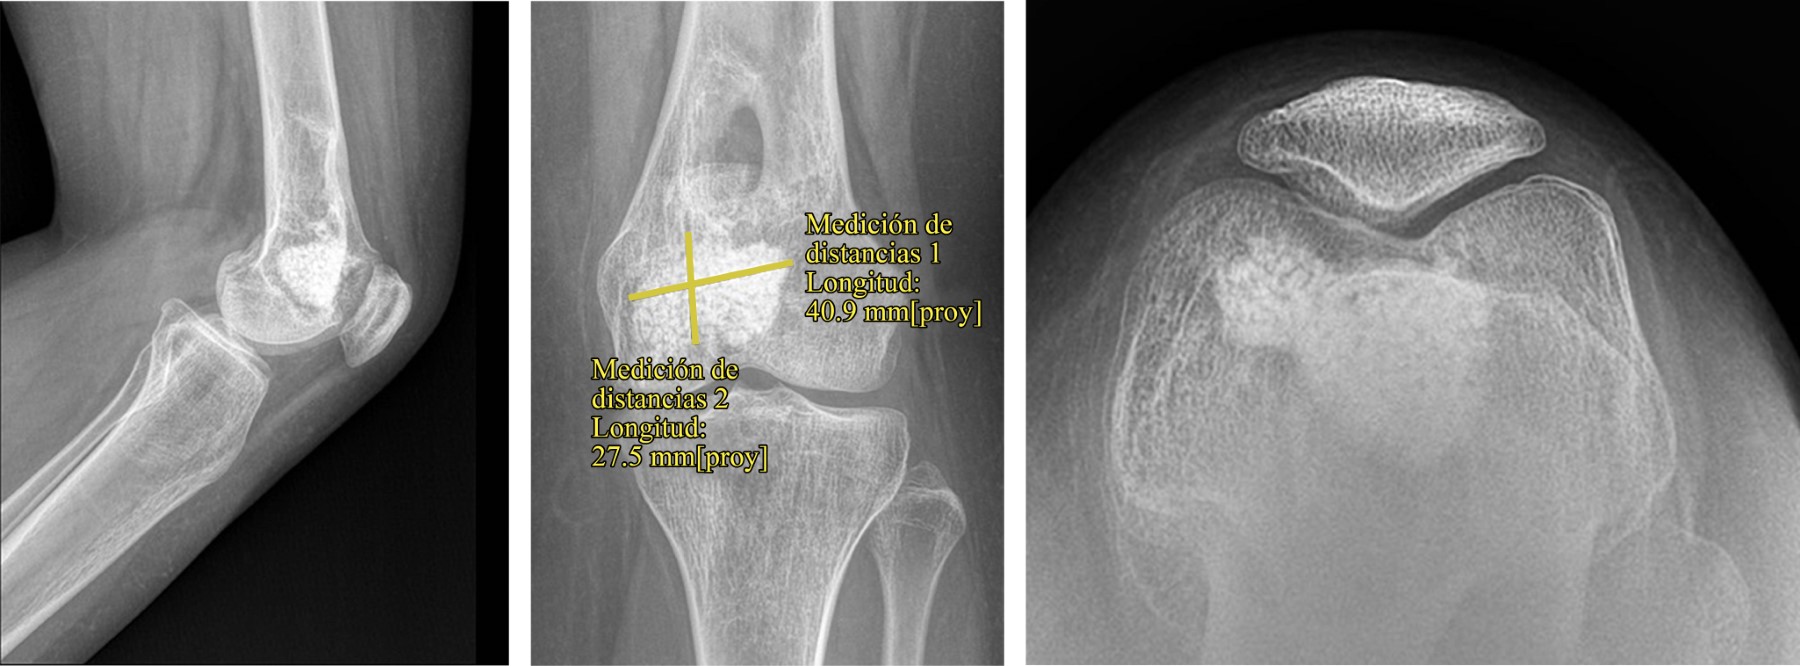

Se trata de paciente de sexo femenino de 15 años y cinco meses, sin antecedentes médicos de importancia. Consultó por primera vez en Julio de 2018 por caída a nivel en escalera, con golpe en rodilla izquierda. Evolucionó con dolor e impotencia funcional inmediata. Al interrogatorio dirigido refirió dolor de tipo insidioso desde hace seis meses, sin antecedente de trauma. Se solicitaron radiografías de fémur derecho anteroposterior y lateral en el servicio de urgencias, las cuales mostraron una fractura en fémur distal izquierdo, con sospecha de fractura en hueso patológico en la metáfisis distal de fémur con imagen que impresiona tener una lesión lítica bien delimitada, con calcificaciones centrales, rodeada por un borde esclerótico delgado sin reacción cortical, con un patrón de pop-corn similar al de un condroblastoma (Figura 1).

Figura 1